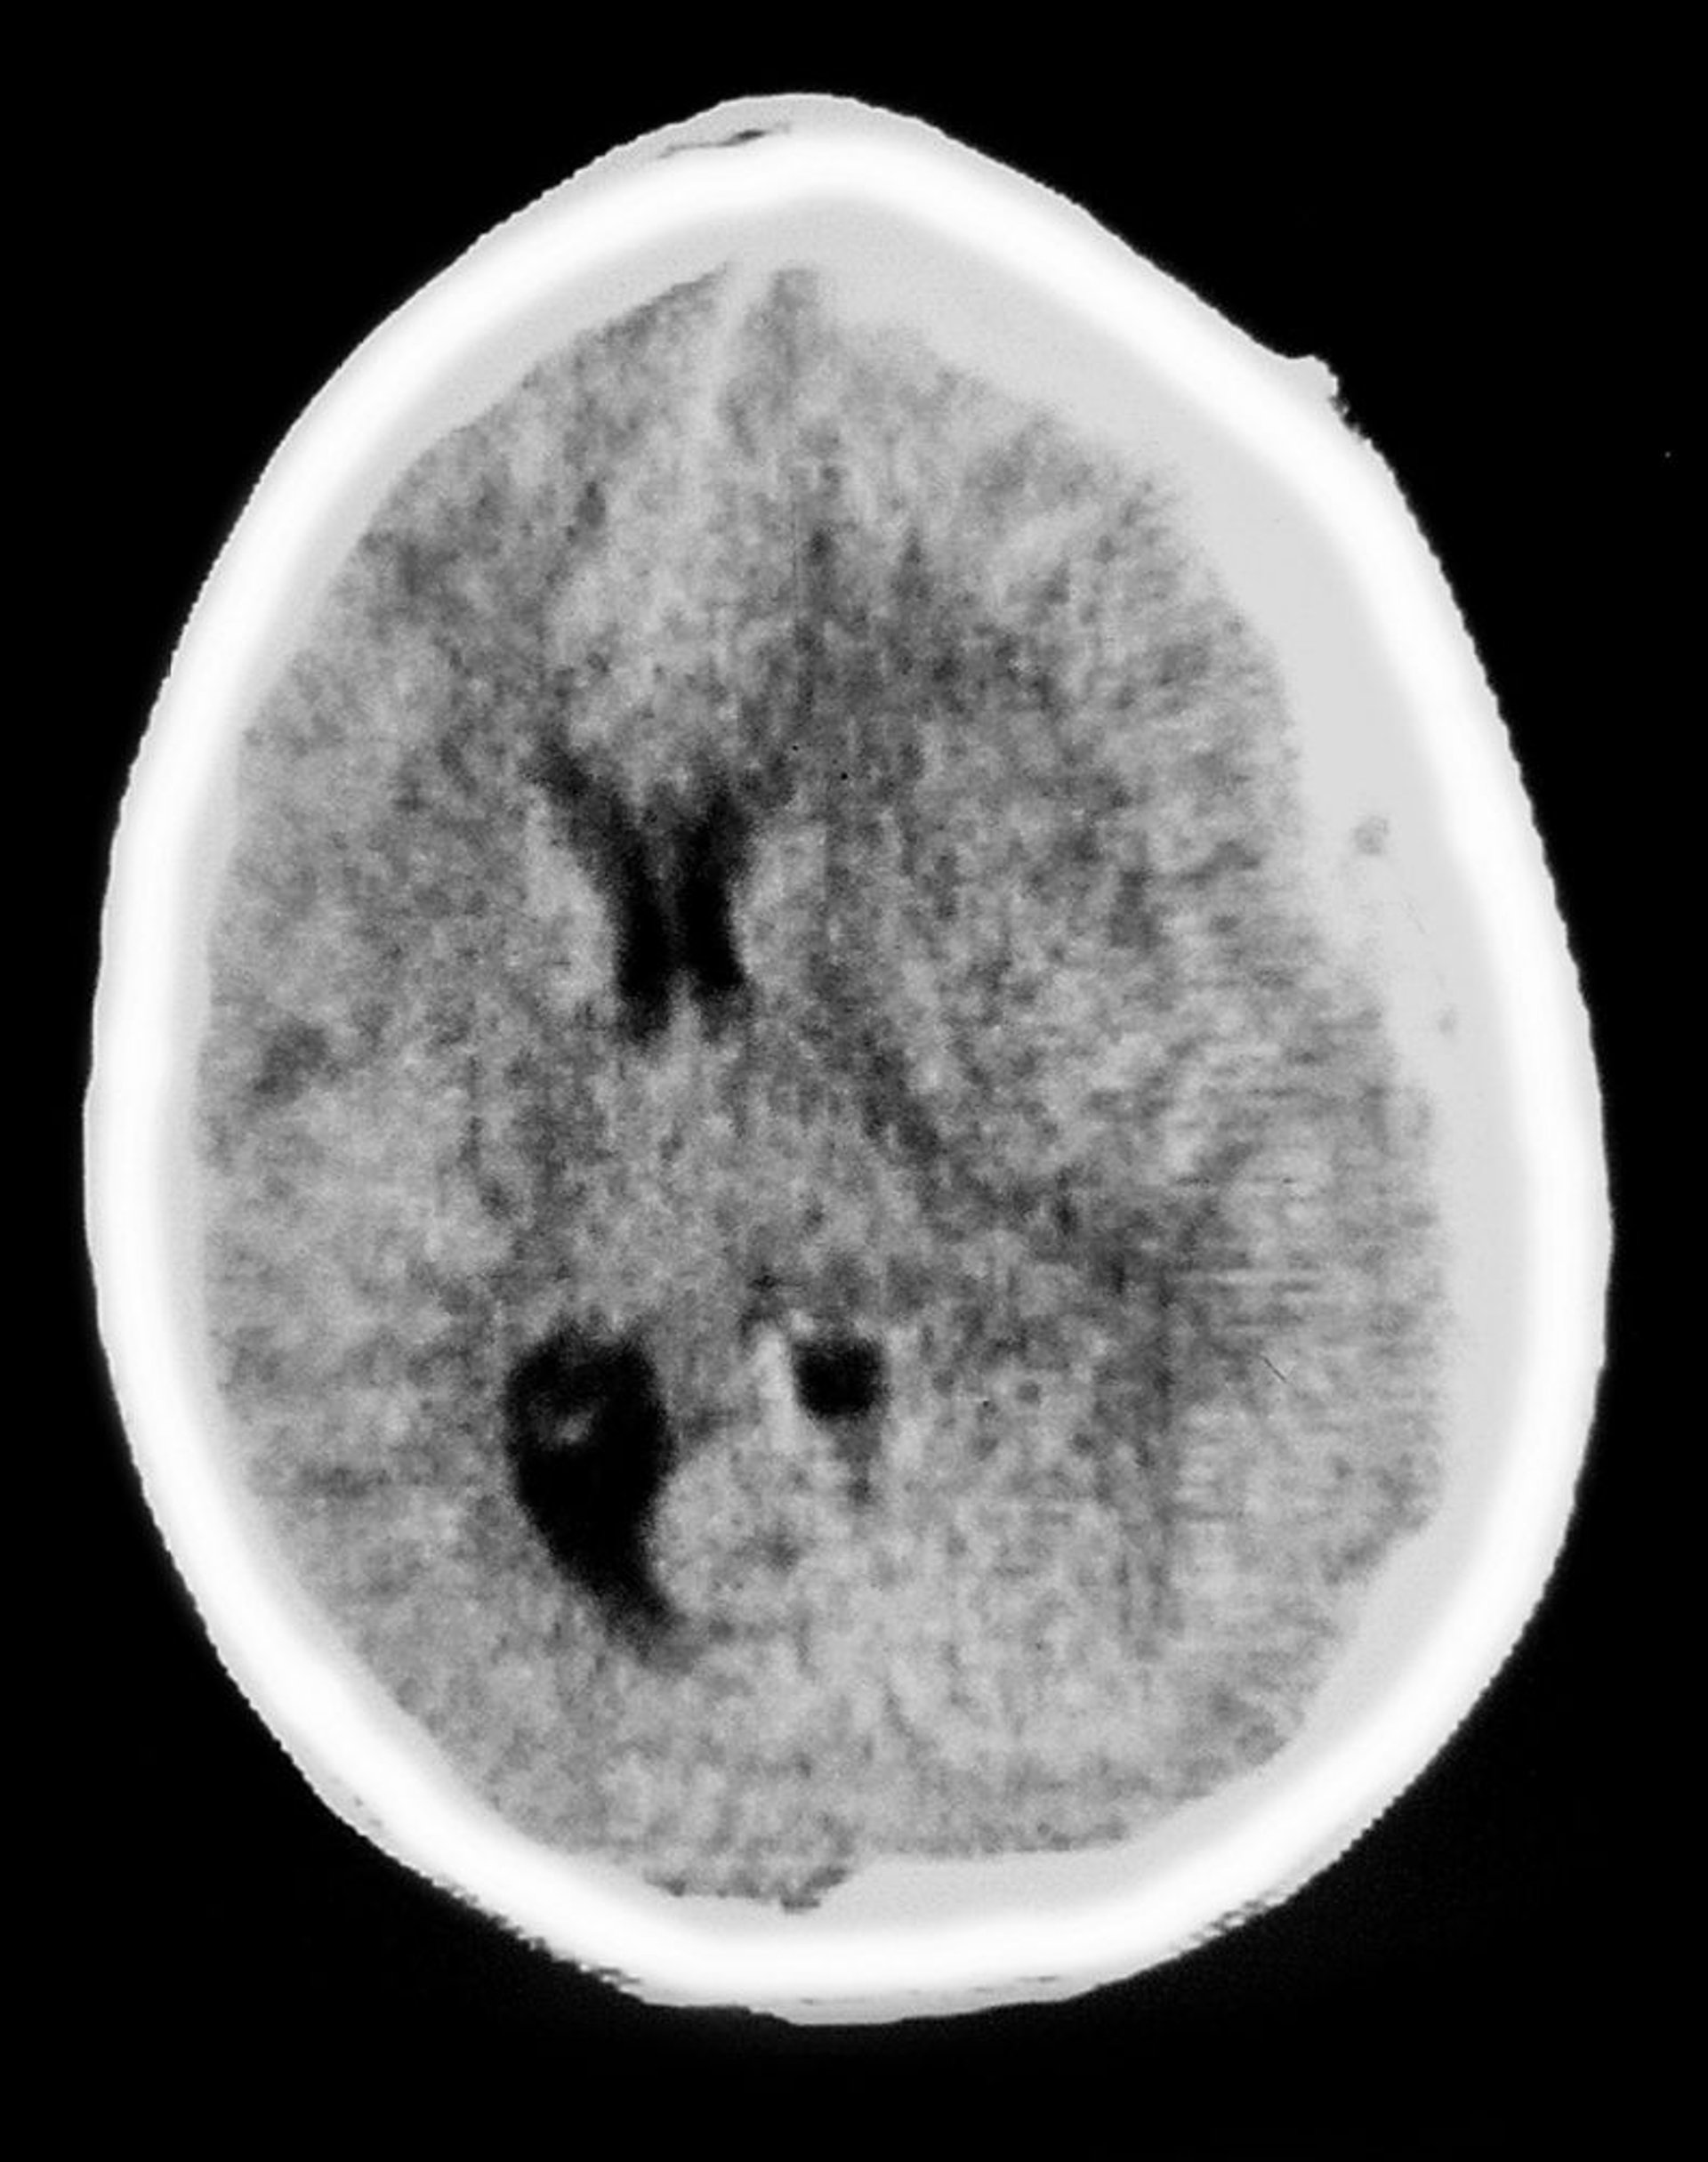

Субдуральная гематома

Это КТ сканирование показывает непрозрачные, характерные для субдуральной гематомы участки в форме полумесяца, покрывающие ткань мозга. Также выражен масс-эффект со сжатием желудочков и смещением средней линии.